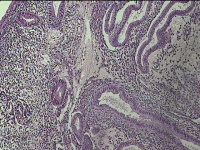

子宫腔内容物

性别

女

年龄

37岁

临床诊断

子宫内膜息肉

一般病史

阴道流血多3个月。

标本名称

大体所见

灰白暗红色不规则碎组织2.8x2.5x0.8cm一堆。